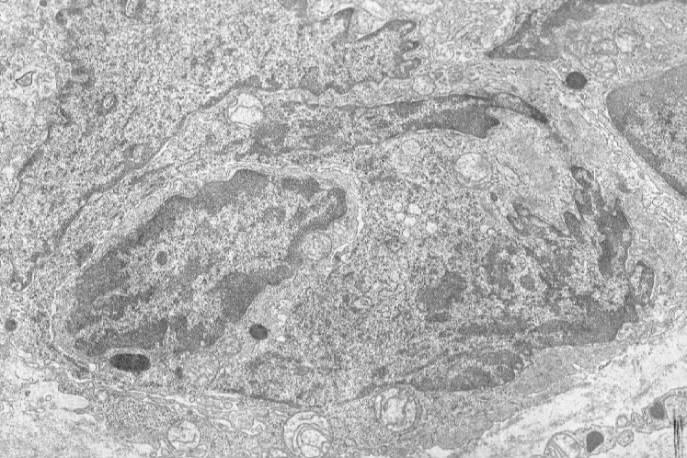

Operation specimen (jpg.20KB) (OMH 98-0339): Primary pulmonary artery sarcoma, open thoracic surgery - intimal sarcoma (HE stain [jpg.44KB]), with involvement of the pulmonary valve. Electron microscopic examination reveals elongated cells (jpg.52KB) and occasionally multipolar giant cells (jpg.75KB) with irregulary indented nuclei, whose cytoplasm contains electron-dense inclusion bodies that measure 500 nm in largest diameter (jpg.46KB), suggesting of lysozomal origin but being somewhat similar to neurosecretory granules. No basal lamina is formed near the tumor cells.